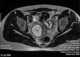

An imperforate hymen is a congenital disorder where a hymen without an opening completely obstructs the vagina. It is caused by a failure of the hymen to perforate during fetal development. [Source: Wikipedia ]